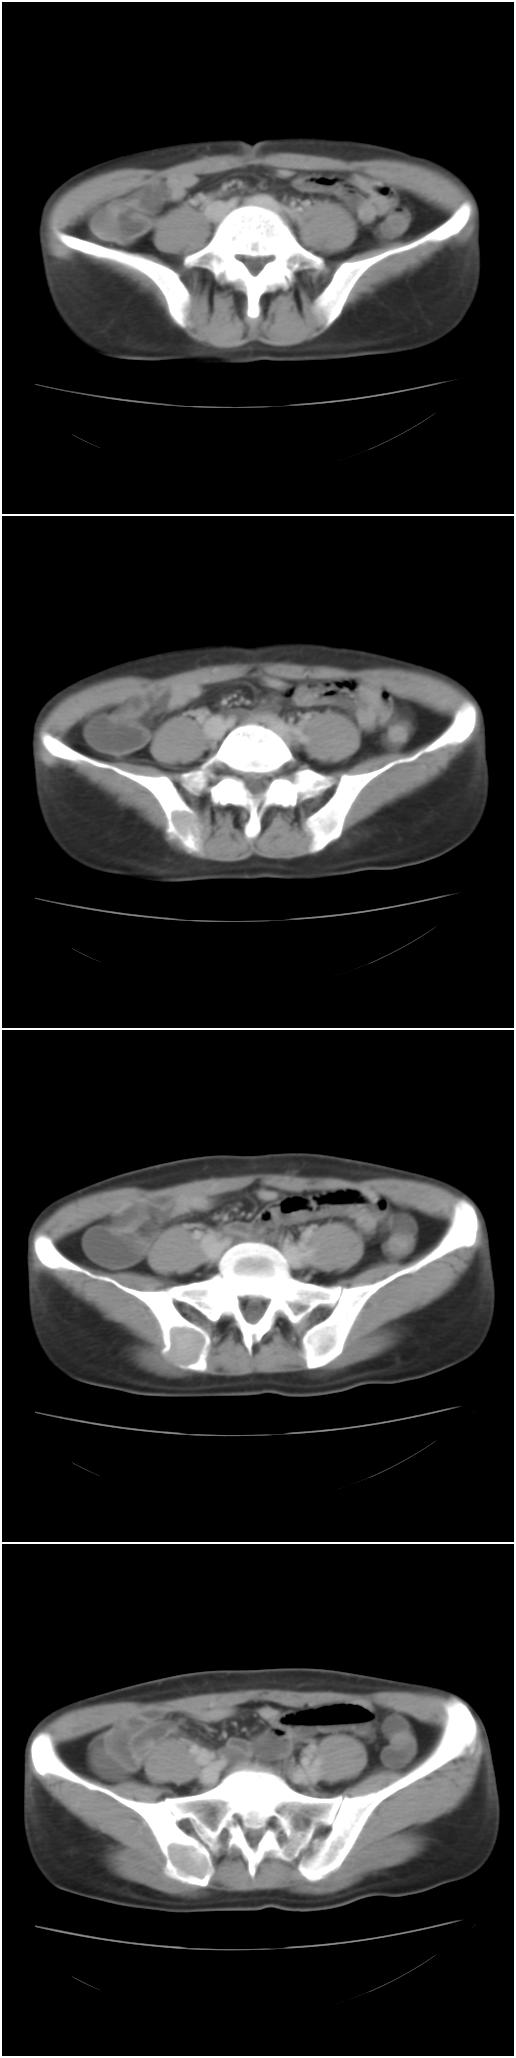

以下是今天的增强片,大家可以看看:

右髂骨见一类圆形略高密度区,似见分层,骨质破坏不明显

考虑良性病变,以动脉瘤样骨囊肿可能性大

右侧髂骨后缘囊状膨胀性骨质改变,无明显骨间隔,周围无明显硬化及骨膜反应,周围软组织无异常,相邻骨组织密度增高,考虑:动脉瘤样骨囊肿可能,要注意与骨巨细胞瘤及转移瘤鉴别。

右侧髂骨膨胀性骨质破坏区 囊内密度尚均匀 骨巨细胞瘤可能性大 动脉瘤样骨囊肿不除外 建议mr观察囊内成分明确诊断 左侧附件区包裹性积液

该病人今天做了增强,右侧髂骨病灶明显强化。

右侧髂后上棘局限性囊状骨质破坏,大部分界清,似见轻度硬化边,内无分格及钙化,病灶上部局部显示模糊。考虑;骨巨细胞瘤可能大,不除外abc。另可见子宫肌瘤术后子宫缺如。

临床和影像学表现:女性患者46岁,有子宫肌瘤手术病史。影像所见可见残余宫颈部分,左右附件未见新生物;右髂骨翼后端囊状膨胀性骨破坏,囊性部分感觉有强化(楼主标上增强前后的ct值就很好了),未见明确的液—液平面,周边硬化不明显或轻度硬化。

分析:患者年龄46岁,没有明确外伤病史,病变呈膨胀性骨破坏,囊性部分未见明确的液—液平面,周边硬化不明显。综合分析该病例比较符合骨巨细胞瘤,不太符合动脉瘤样骨囊肿。

诊断:1、首先考虑骨巨细胞瘤;2子宫肌瘤术后改变